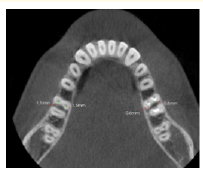

Role of CBCT in the Success of BSSO in Patients with Thin Ramus

Thenaruvi Marimuthu. 22(7): 71-73.